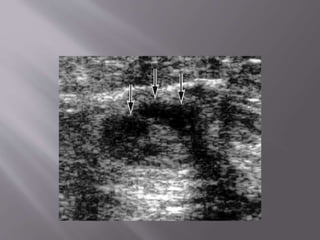

The lump (arrow) in this

patient’s right breast was

Using ultrasound guidance, a fine

needle (white line) is placed so

that its tip (double arrow) is in the

center of the lump (single arrow).

Aspiration is applied by using a

syringe attached to the needle. If

this is a cyst, fluid is drawn into

the syringe as the lesion collapses.

After the aspiration, the

needle (white line) and its

tip (double arrow) are

seen, but the lump is gone.